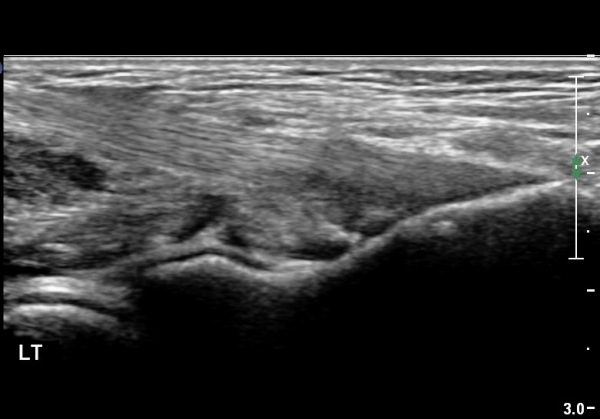

ÁÂÃø ÀÌµÎ¹Ú±Ù°Ç ¸»´Ù´© Ⱦ´Ü¸é°Ë»ç¿¡¼­ À̵ιڱÙÀü ºÎÁ¾ÀÌ °üÂûµÊ(±×¸² 8).